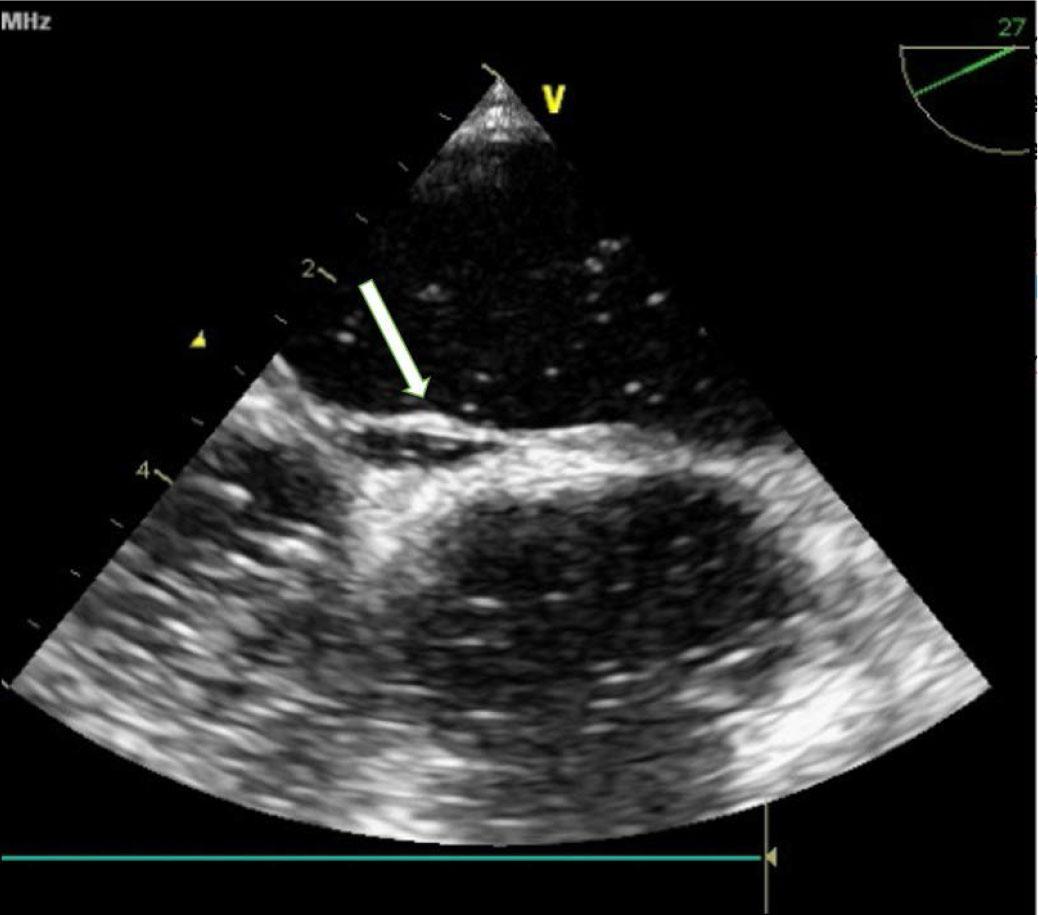

FIGURE 1.